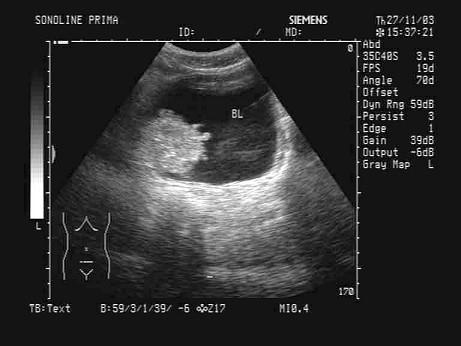

问题 男性,60岁,排尿不适,无痛性血尿,膀胱声像图如图,根据图中表现及所标志的体位,最可能的超声诊断为?(?)

选项 A.膀胱息肉 B.膀胱结石 C.膀胱癌 D.膀胱血块 E.前列腺癌

答案 C